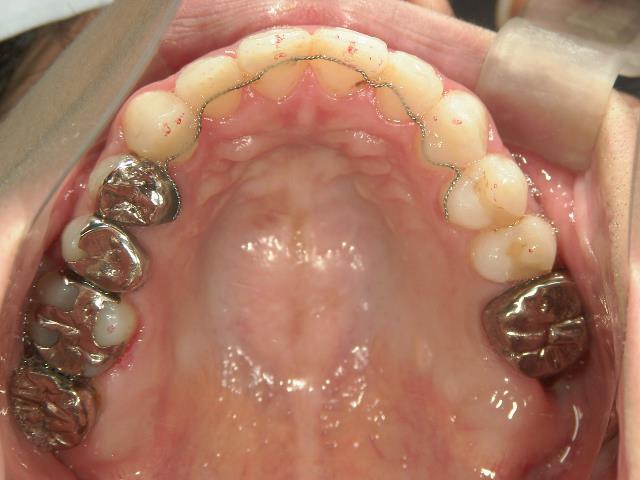

矯正歯科 治療後

矯正_灰色.pngno.28_6958_治療後_上.jpg矯正_灰色.png